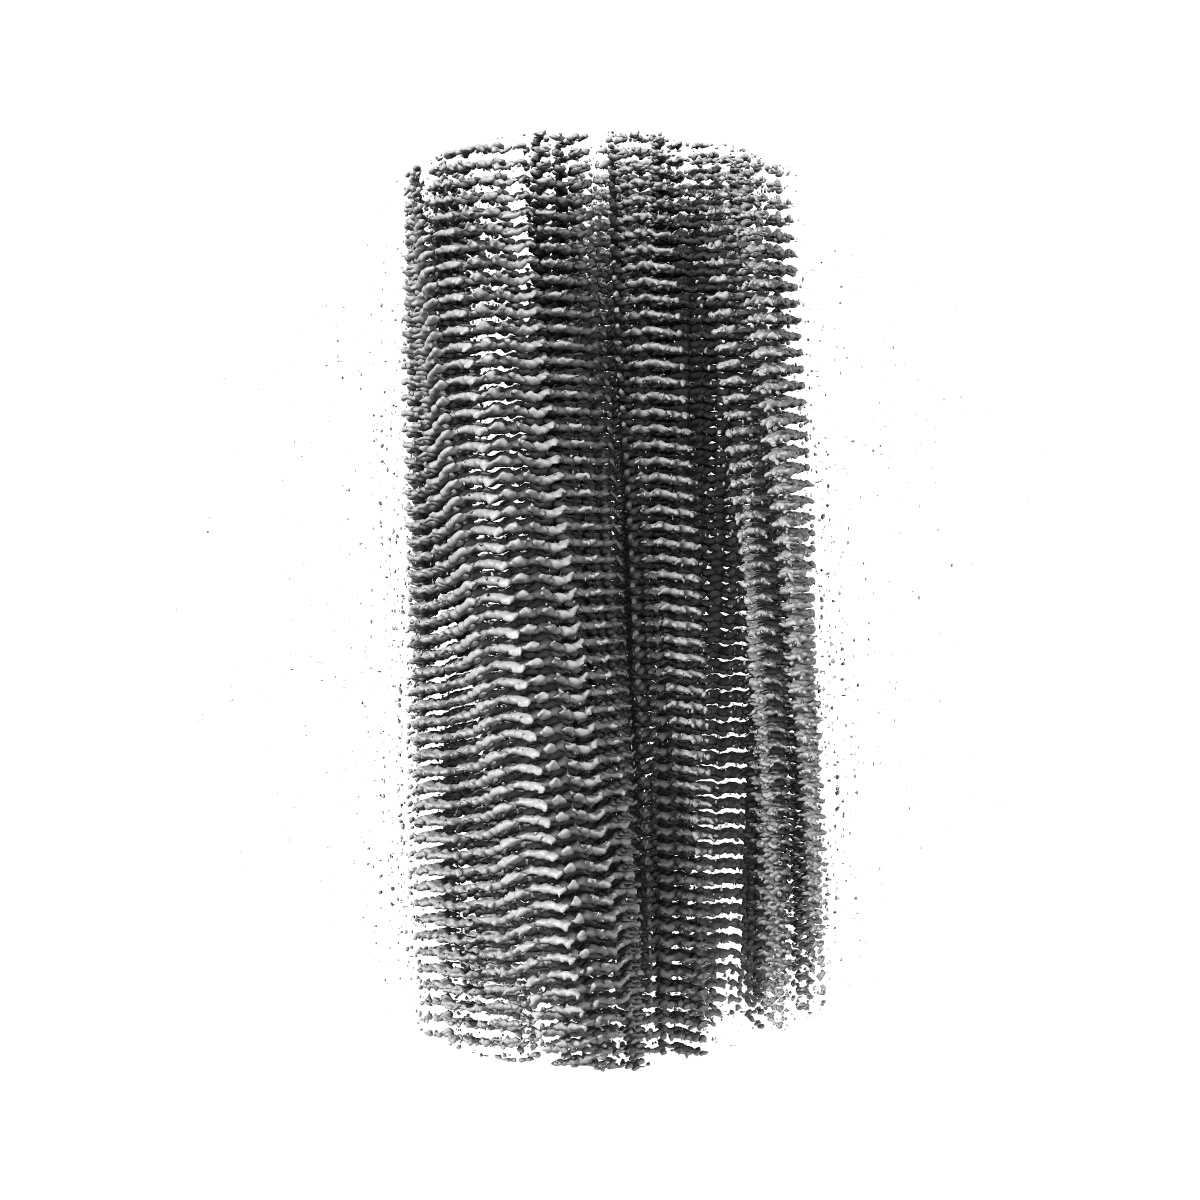

EMD-18259

Tau - AD-THF

Helical reconstruction

2.68 Å

Sample Organism: Homo sapiens

Sample: Amyloid

Fitted models: 8q8s

Deposition Authors: Lovestam S, Li D , Scheres SHW , Goedert M

Disease-specific tau filaments assemble via polymorphic intermediates.

Lovestam S, Li D , Wagstaff JL, Kotecha A , Kimanius D, McLaughlin SH , Murzin AG, Freund SMV , Goedert M , Scheres SHW

(2024) Nature , 625 , 119 - 125